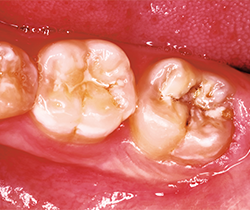

After occlusion is adjusted and restorations are finished and polished with OptraPol polishing cups and points (Ivoclar Vivadent), final radiographs and photos are taken to demonstrate the radiopacity of the material, the ideal interproximal contours and sealed margins, and its monolithic, void-free qualities (Figs. 16-20).

Fig. 18 Fig. 19